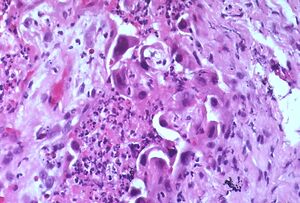

اللانمطية (إنگليزية: Atypia)، [1] هو مصطلح يستخدم في علم الأمراض لوصف الخلايا التي تبدو غير طبيعية سواء في الشكل أو اللون أو الحجم مقارنة بالخلايا السليمة والعادية في نفس الموقع. قد يصف أخصائيو علم الأمراض أيضًا هذه التغييرات على أنها انمطية خلوية أو خلايا غير نمطية.

السمات التي تشكل اللانمطية لها تعريفات مختلفة لأمراض مختلفة ، ولكنها غالبًا ما تتضمن تشوهات النواة[4]

- العديد من الاشكال الانقسامية الانفتالية